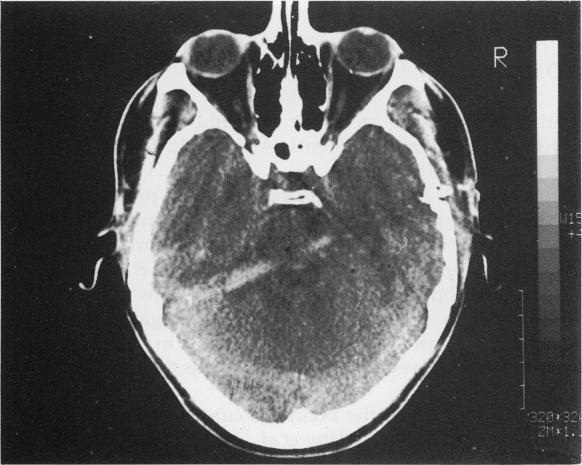

Because injury to the brain stem is usually associated with diffuse brain damage, recovery is rare and mortality high. A non-fatal penetrating injury involving the brain stem is described from a crossbow bolt. The diagnosis and management of such injuries are discussed.

https://cdn.ncbi.nlm.nih.gov/pmc/blobs/c604/1285706/e4eab5fd7381/archemed00027-0099-a.jpg